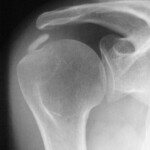

Στὴν ἀκτινογραφία παρατηροῦνται μικρὲς ἀσβεστώσεις στὴν κατάφυση τοῦ τένοντος τοῦ ὑπερακανθίου μυός στὸν ὦμο (ἔξω ἀπὸ τὸ ὀστοῦν, στὰ μαλακὰ μόρια). Μικρὲς μὲν ἀλοιώσεις ἀλλὰ τόσο σημαντικές, ποὺ δημιουργοῦν ἔντονουςπόνους, σὲ σημεῖο νὰ ἀδυνατεῖ ὁ ἄνθρωπος νὰ ἐπιτελέσει σημαντικὲς γιὰ τὸν ἴδιο κινήσει, ἀλλὰ καὶ ἄλλες ποὺ δὲν μεταφέρονται μὲ εἰκόνες (τίναγμα σεντονιῶν, ξεσκόνισμα, χτένισμα, λούσιμο, κούμπωμα-ξεκούμπωμα σουτιέν, ντύσιμο, φερμουὰρ πλάτης, ἀτομικὴ καθαριότητα στὴν τουαλέττα κ.ἄ).

Εἶναι ἡ ἀσβεστοποιὸς τενοντῖτις ὤμου (Tendinosis calcarea) ἢ περιαρθρῖτις ὥμου, ποὺ ἀποτελεῖ καὶ τὸ 16% τῶν μυοσκελετικῶν πόνων τοῦ ἀνθρώπου, 2η σὲ συχνότητα μετὰ τοὺς πόνους τῆς μέσης.